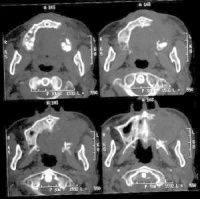

4.X线摄片示上颌窦腔密度增高、软组织肿块影及窦壁骨质破坏

详细检查前后鼻腔,大多数病例有鼻腔异常,鼻腔外侧壁内移致鼻总道狭窄。当瘤侵入鼻腔时可通过前鼻孔或后鼻腔检查直接窥见。瘤体位于鼻腔侧壁或顶壁,呈灰红色,表面粗糙;或呈烂肉状,触之易出血;有时表面覆有污秽灰膜,伴组织坏死。鼻中道或鼻下道可见血性分泌物或血痂,或见鼻息肉样肿块,实为恶性肿瘤。因息肉样变与鼻息肉可与上颌窦肿瘤并存。因此,体格检查往往可早期发现异常表现,若鼻腔检查无特殊,也不能完全除外上颌窦恶性肿瘤,只要有临床症状,则宜作进一步检查。